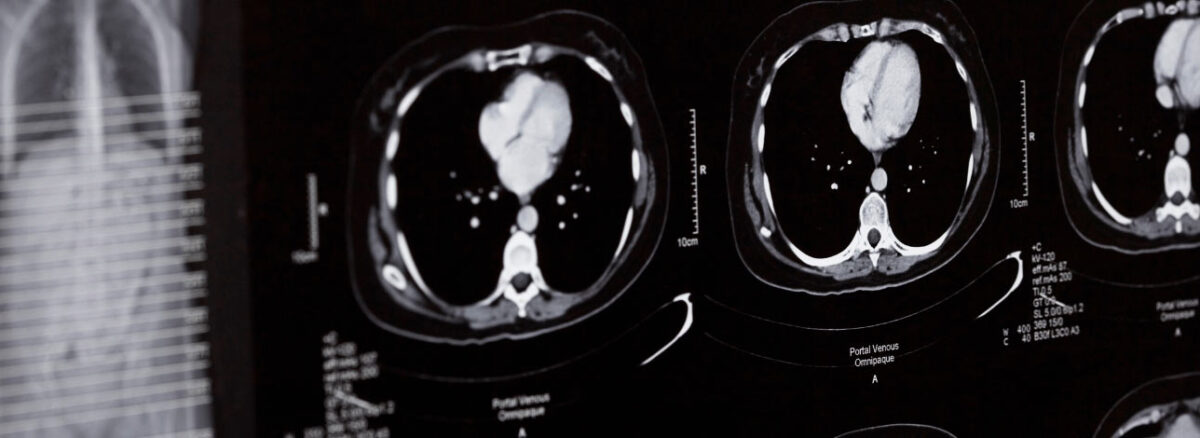

Tal projeto pode propor métodos inovadores na detecção, tratamento e prevenção de doenças, incluindo o câncer

Um projeto guiado pelo programa UK Biobank está prestes a realizar uma nova análise dos cérebros e corpos de 60 mil voluntários do Reino Unido, com o objetivo de descobrir novas abordagens para tratamento e prevenção de doenças. Essa ação é financiada pelo Medical Research Council, Wellcome Trust, British Heart Foundation e Dementias Platform UK.

Em síntese, através da observação do envelhecimento do corpo, o estudo pode ajudar a identificar quem tem maior probabilidade de desenvolver demência ou diferentes tipos de câncer. Além disso, os resultados da pesquisa já geraram um teste genético capaz de identificar pessoas com maior risco de doença cardíaca coronária.